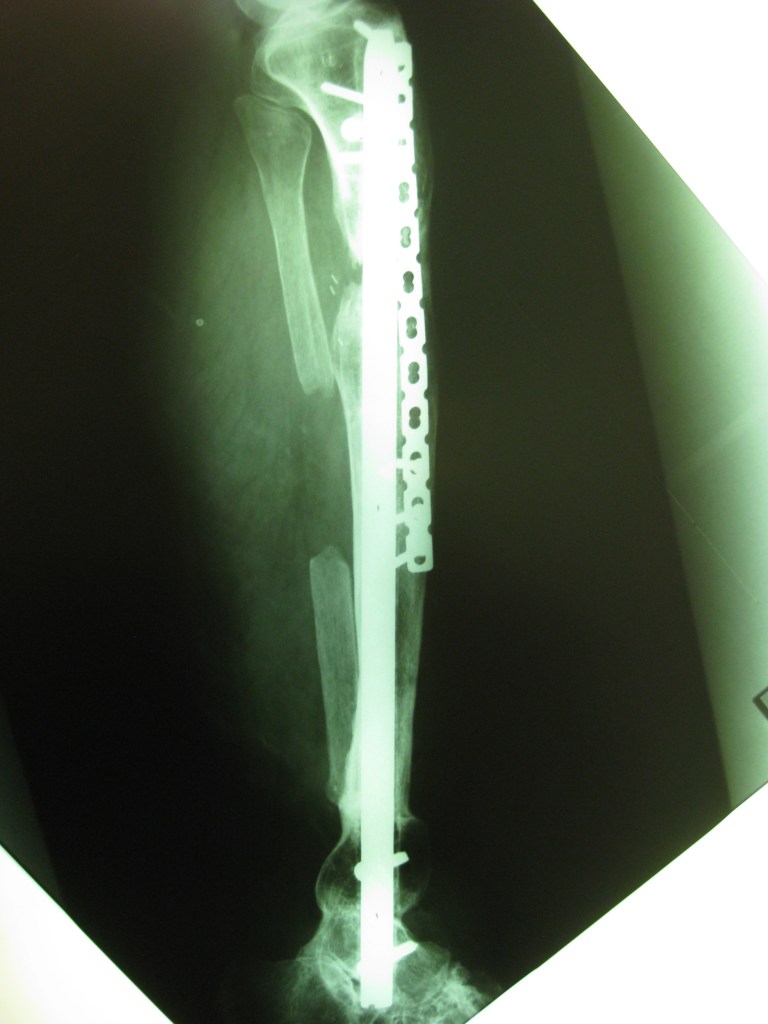

Deformidad grave de pierna con acortamiento oseo e infección

Luego de 10 años de cirugías en distintos centros del país , mi única opción era realizarme una amputación

Luego de consultar con el Dr Dratewka y su Equipo , me explicaron la necesidad de varias cirugías en etapas para tratar mi infección , corregir mi pie y devolver el largo de mi pierna

No tengo palabras para lo que me hicieron y ayudaron ,me sentí acompañada en todo momento y ahora puedo decir que no duden en hacer una consulta si tienen dudas sobres su problema